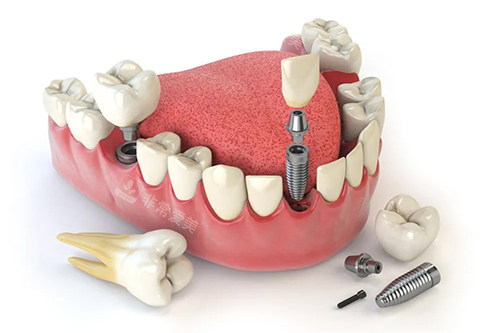

牙齿种植卡通示意图